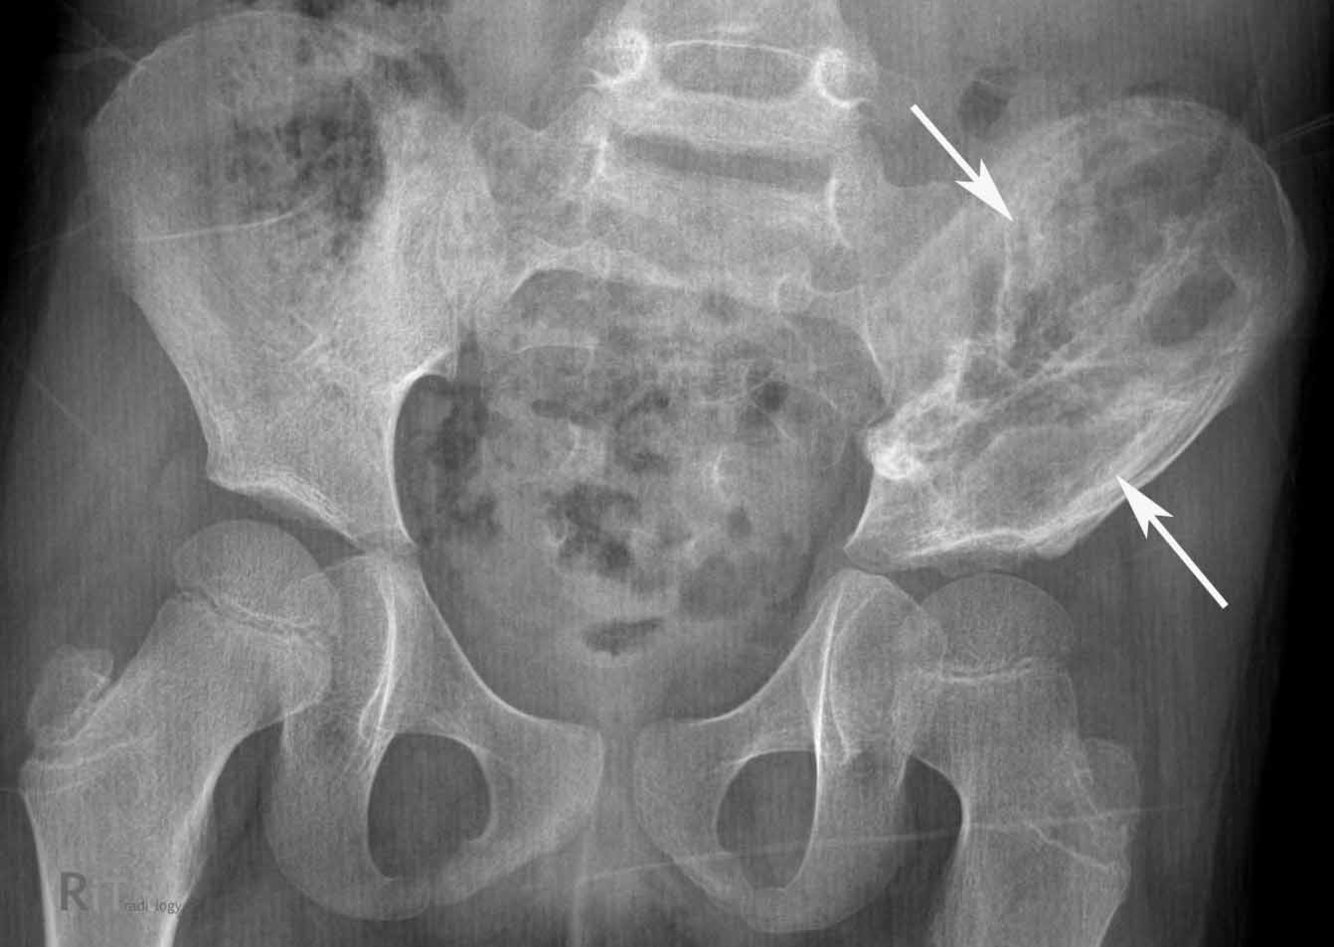

12 yo male comes in with fever, and painful left hip. Below is his XR. Diagnosis? Managment? Treatment?

Ewing Sarcoma